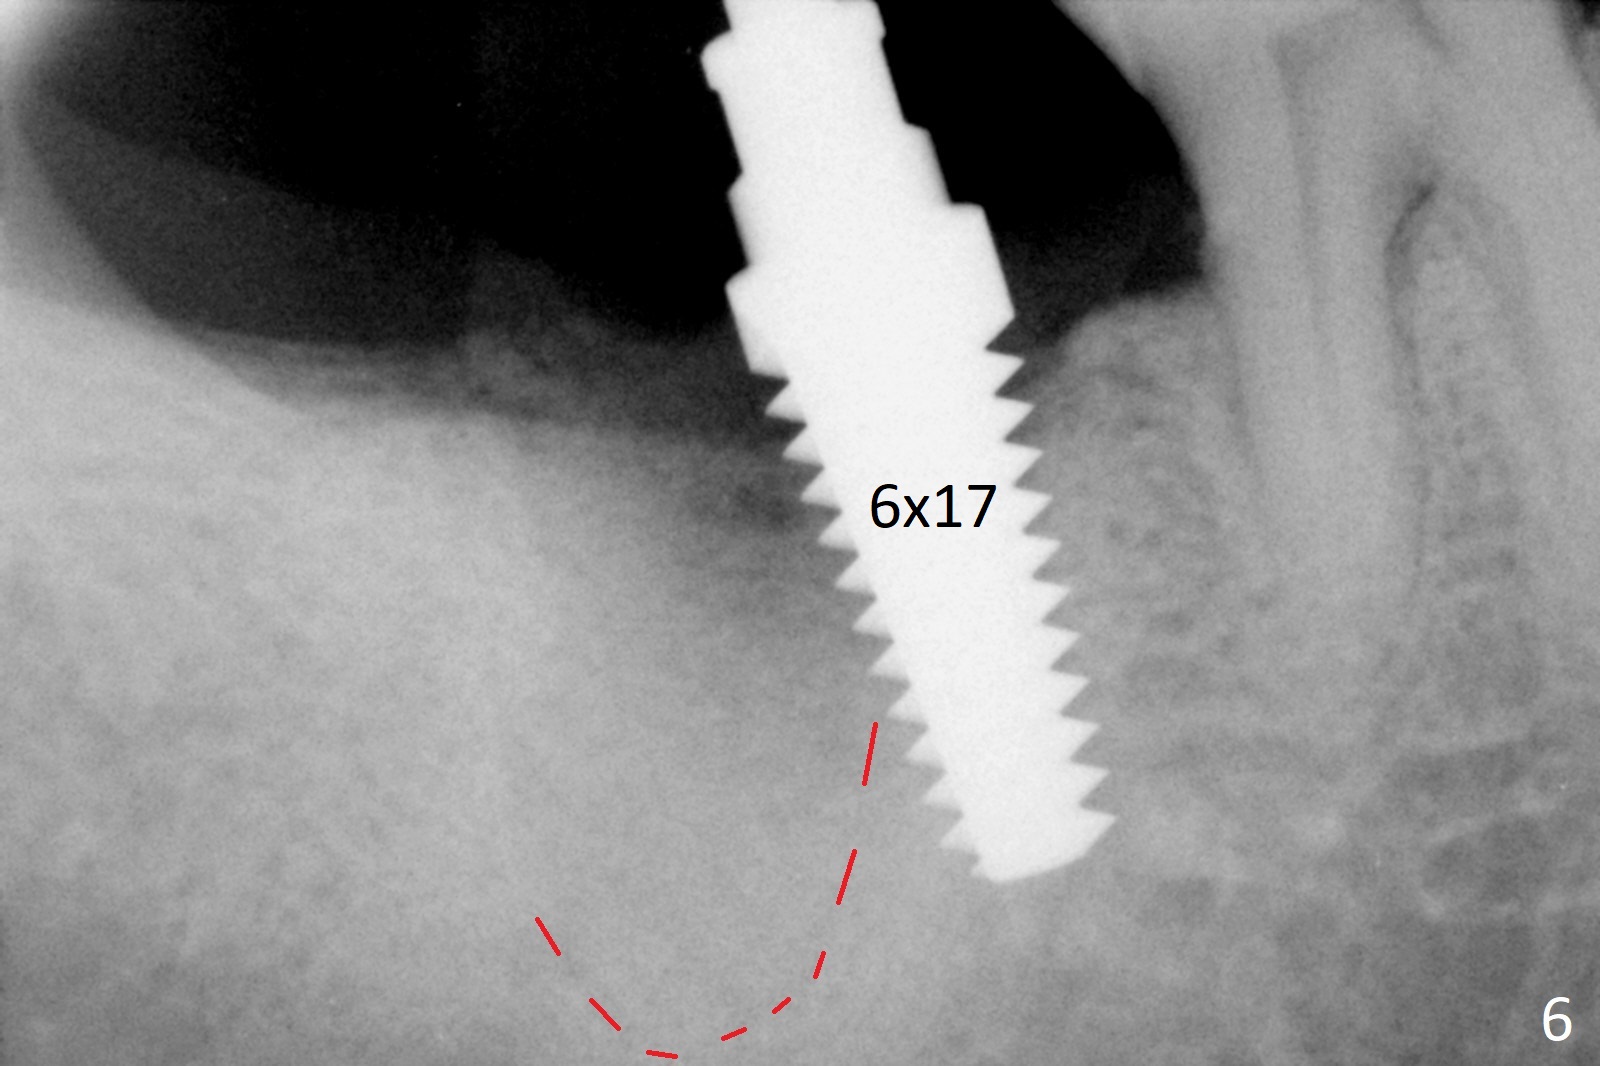

A 50-year-old man, a smoker, presents to clinic with pain of the tooth #15 with apparently occlusal trauma (Fig.1). Two years and three months after #15 extraction, he returns for #31 extraction (Fig.2) and socket preservation (Fig.3). The socket depth is 17 mm along the long axis of the socket 2.5 months post extraction (Fig.4, gingival level). Initial osteotomy is created in the mesial slope of the socket for 14 mm (Fig.5). After sequential osteotomy, a 6x17 mm tap is seated shallower (Fig.6) than the 2 mm drill (Fig.5). Following further osteotomy, a 7x14 mm implant is seated incompletely (Fig.7), which was not found intraop. The implant becomes loose with purulent discharge 19 days postop. The patient returns for 2nd placement 2 months post implant removal (Fig.8). Osteotomy is created probably in the mesial slope with 17 mm (bone level, Fig.9). After insertion of 5 (Fig.10) and 6 (Fig.11) x20 mm taps (tissue level), a 6x20 mm tissue-level implant is placed with clearance from the Inferior Alveolar Canal (Fig.12 yellow dashed line). The implant is restored 8.5 months postop (Fig.13) without bonding 5 mm 0 degree unipost. The crown dislodges 4 months post permanent cementation. Still the patient complains of small crown without occlusal contact. Impression is taken for a new normal-sized crown. The new crown becomes loose 1 year 9 months post cementation (Fig.14). The teeth #14 and 15 remain unrestored.